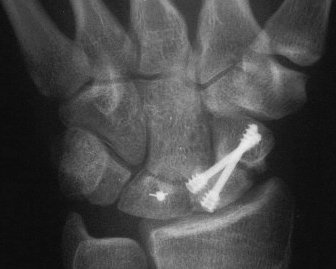

Case 2. Nonunion with a large fracture cyst. After debridement, the defect, the graft, and yes, that is the capitate peeking through the defect.

The graft, and inadequate seating of the more ulnar screw.